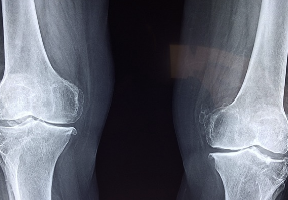

콘드로이친 1일권장 섭취량과 효능 및 부작용 알아봐요 콘드로이친 효능 및 부작용 등 콘드로이친과 관련된 정보 알아보도록 하겠습니다.콘드로이친(Chondroitin)은 연골 조직과 결합되어 있는 큰 분자인 그리코사미노글리칸의 일종입니다. 연골 조직을 형성하는 세포들이 만들어내며, 연골의 탄성과 내구성을 유지하고 연골 조직의 재생과 보호를 돕는 역할을 합니다. 또한 염증 억제 효과가 있어 관절염 등의 염증성 관절질환의 치료에도 사용됩니다.

- 연골 보호: 콘드로이친은 연골 조직의 재생과 보호를 돕는 역할을 합니다. 연골 조직은 연령이 들면서 파괴되는 경향이 있으며, 적절한 콘드로이친 섭취는 연골 조직의 파괴를 줄여주어 건강한 연골 조직을 유지하는 데 도움을 줍니다.

- 관절 염증 억제: 콘드로이친은 염증 억제 효과가 있어, 관절염 등의 염증성 관절질환의 치료에 효과적입니다.

- 관절 윤활: 콘드로이친은 관절 내 윤활제 역할을 하여 관절 부위의 마찰을 감소시켜 관절 통증을 완화시키고, 관절의 움직임을 개선시킵니다.

- 연골 탄성 향상: 콘드로이친은 연골 조직의 탄성과 내구성을 증가시켜 관절 내부의 충격을 완화시켜 줍니다.